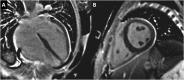

"Cases of SCMR" is a case series on the SCMR website (https://www.scmr.org) for the purpose of education. The cases reflect the clinical presentation, and the use of cardiovascular magnetic resonance (CMR) in the diagnosis and management of cardiovascular disease. The 2022 digital collection of cases are presented in this manuscript.